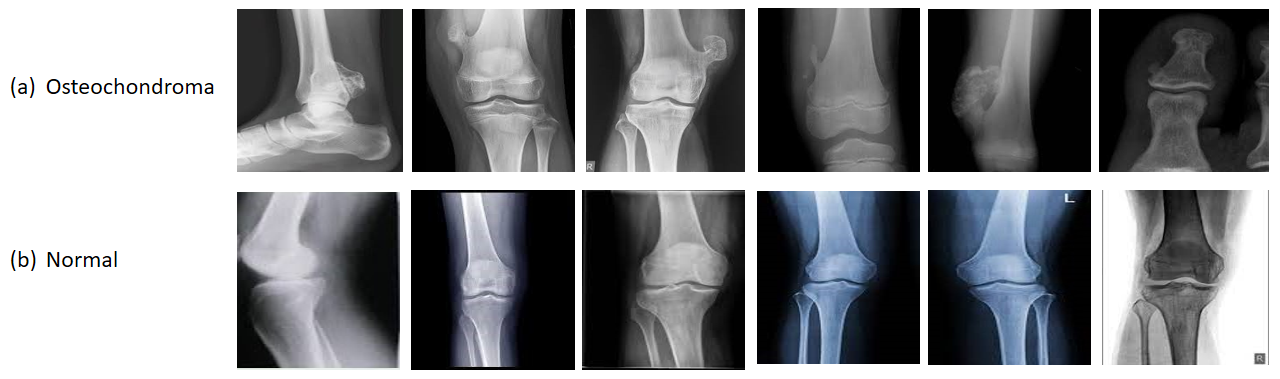

Osteochondroma Identification Through Transfer Learning and Convolutional Neural Networks

Ayesha Afridi, Muhammad Kamran Abid, Naeem Aslam, Shumaila Khan, Arsalan khan, Muhammad Ahmad Nawaz Ul Ghani

608-620